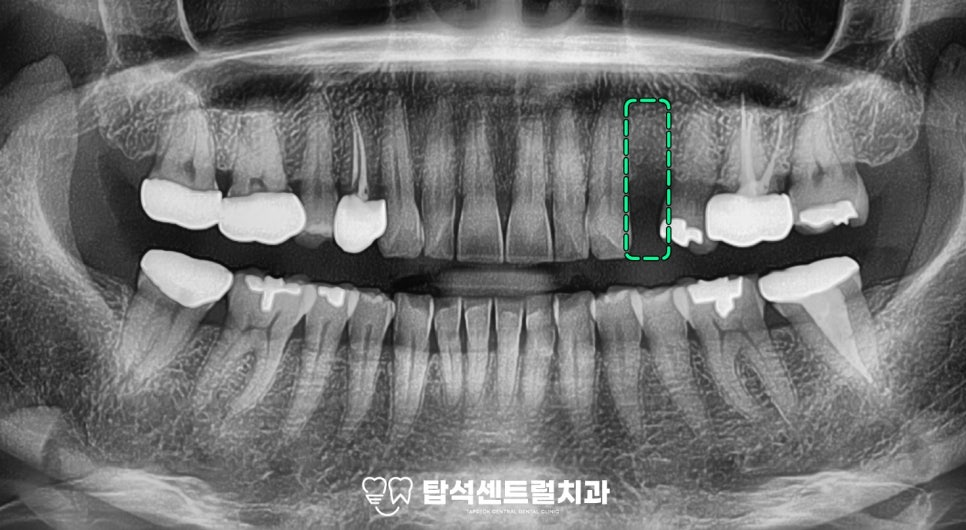

정면 모습을 보면

왼쪽 위 작은 어금니가 있어야 되는 곳의

치은이 푹 들어가 있는 것을

관찰할 수 있습니다.

측면에서 보면

푹 들어간 것이 확실히 보입니다.

교합면을 보았을 때

아직 완전히 아물지 않은 것으로

판단되었으며,

엑스레이를 보았을 때는

한 달쯤 전에 발치를 하신 것으로

판단할 수 있었습니다.

완전히 회복된 것을 아니지만

뼈와 치은의 폭이 모두 양호한 편에

속하였는데요.